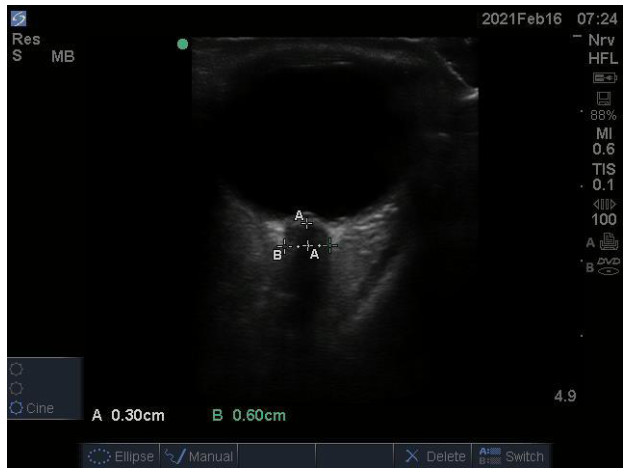

1.3 超声测量方法患者于术后12 h使用便携式彩色超声诊断仪M-Turbo(FUJIFILM SonoSite,博塞尔市,美国)测量ONSD。超声测量时,患者取仰卧位,透明敷贴保护双眼,头居中,使用高频(6~13 MHz)线阵探头,涂抹凝胶后,将探头轻放于患者闭合的眼睑上,对眼球后方3 mm处的视神经鞘进行测量,双眼扫描方向包括横断面和矢状面,各进行3次扫描,取平均数,精确至0.1 mm。ONSD测量由同一名经过床旁超声测量ONSD培训的重症医学科医生完成。见图 1。

| 图 1 超声测量视神经鞘直径示意图 Fig 1 Ultrasound measurement of optic nerve sheath diameter |